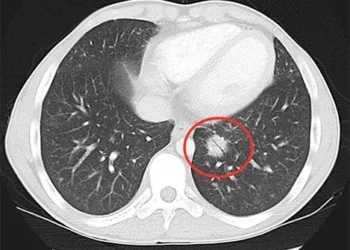

Paciente no Reino Unido é o primeiro vacinado contra câncer de pulmão

Redação Rios BRASIL - O câncer de pulmão é a terceira doença que mais mata homens e a quarta em ...